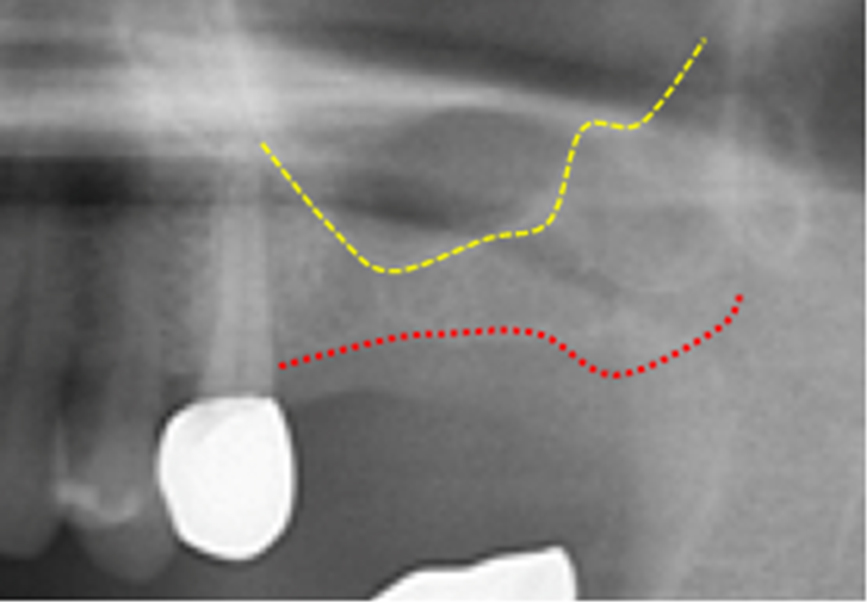

水壓式鼻竇增高術 (圖一)

圖一 /利用水壓之方式提升上顎竇

上顎骨會隨著年齡增長而逐漸萎縮(特別是缺牙已久之區域),造成鼻竇過低進而導致植牙不易;對於較年長之患者來說,水壓式鼻竇增高術相較於其他兩種術式,有著手術傷口較小、術中較不易感到不適及術後併發症風險較低等優點,特別適合於年紀較大之患者。且水壓式鼻竇增高術幾可用於所有上顎骨高度不足之案例,亦可用於多顆植牙區(圖二),目前已逐漸取代前兩者;惟此一術式為較新穎之術式,技術門檻較高,患者治療前宜多方面諮詢評估。

圖二/左圖為治療前之X光,右圖為水壓式鼻竇增高術合併植牙手術後X光。紅色虛線為齒槽骨下緣,黃色虛線為治療前上顎竇下緣,藍色虛線為治療後上顎竇下緣。藍色虛線下方可見緻密且均勻之骨充填。